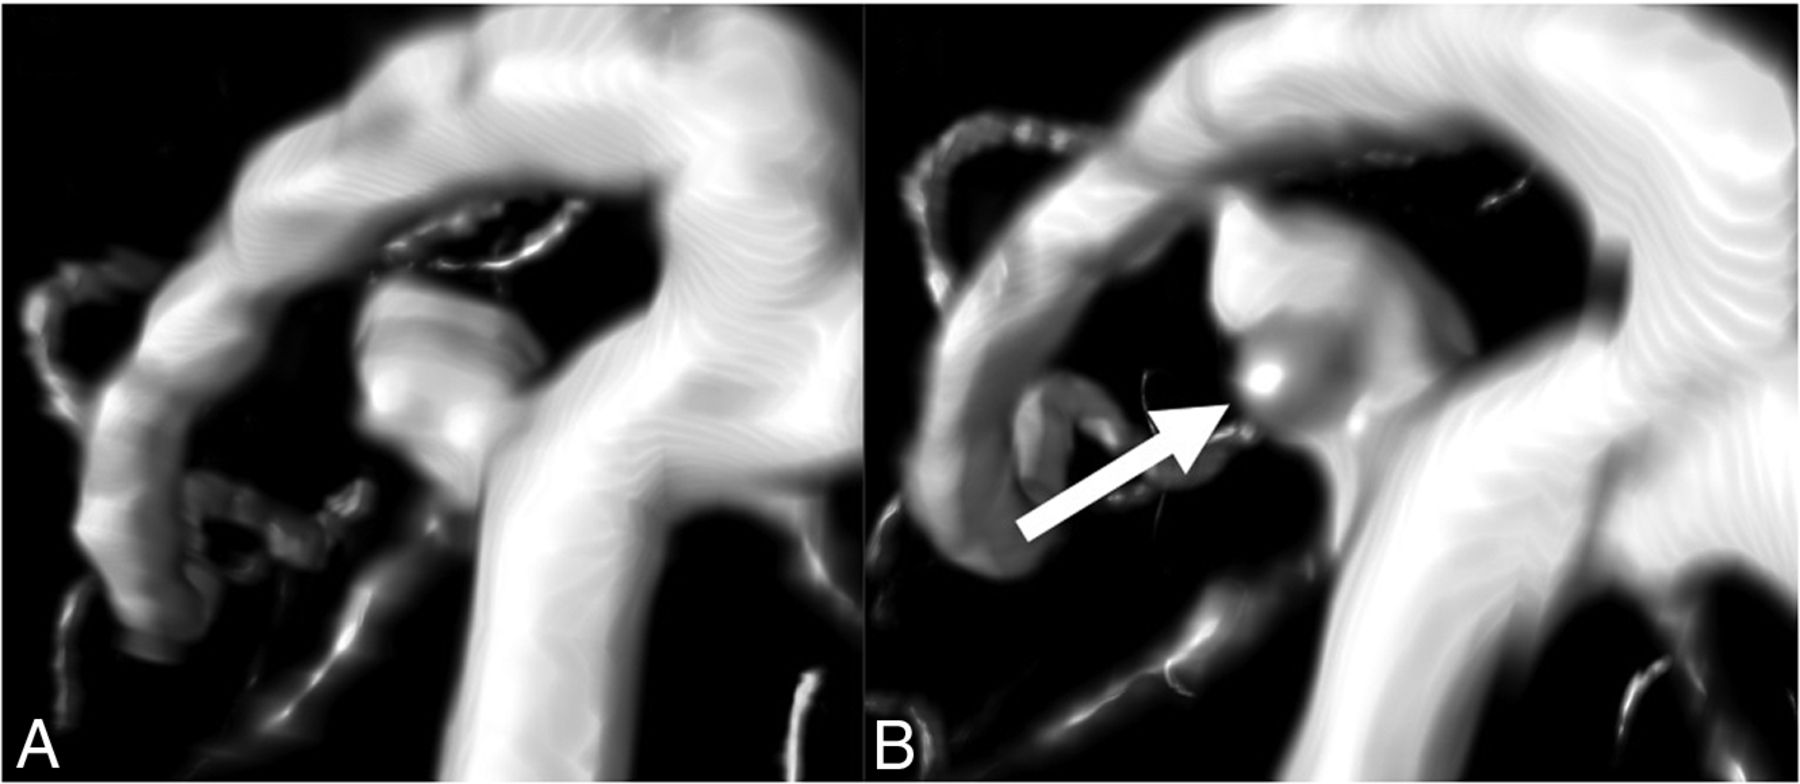

For the parameters flatness, shape index, and curvedness, we determined the proportion of UIAs with morphologic changes that statistically significantly differed from most of the full study population. In total, 18 UIAs (14%) changed statistically significantly in ≥1 of the morphology parameters compared with most of the population. Eight of the 15 growing UIAs (53%) and 10 of the 112 nongrowing UIAs (9%) showed a statistically significant morphologic change (Fig 2).

Nongrowing UIA with statistically significant change in morphology. An example of a ROI around a UIA taken from baseline and follow-up TOF-MRAs made on a Philips 1.5T scanner (Intera/Achieva). The measured UIA shows statistically significant changes in morphology but was considered to be nongrowing (<1-mm change in length or width). The bulge (arrow) that becomes visible on follow-up results in more saddle points on the surface of the UIA, whereby the shape index decreases. The bulge also increases the curvature of the surface of the UIA, resulting in a slightly increased curvedness value.